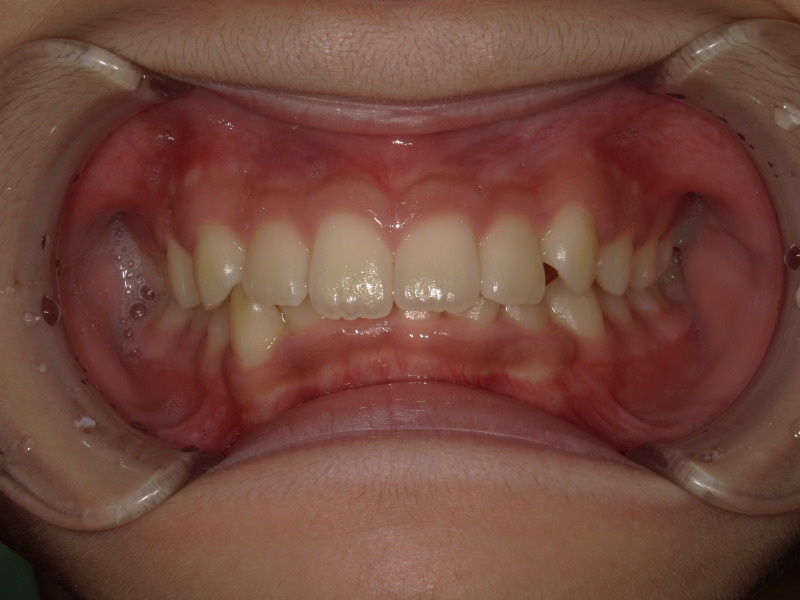

検査時の状態

上下の噛み合わせが深く、強く噛み込んでいるため下の歯が見えていません。

また下の歯並びもがたつきがあります。

この時既に全て永久歯です。